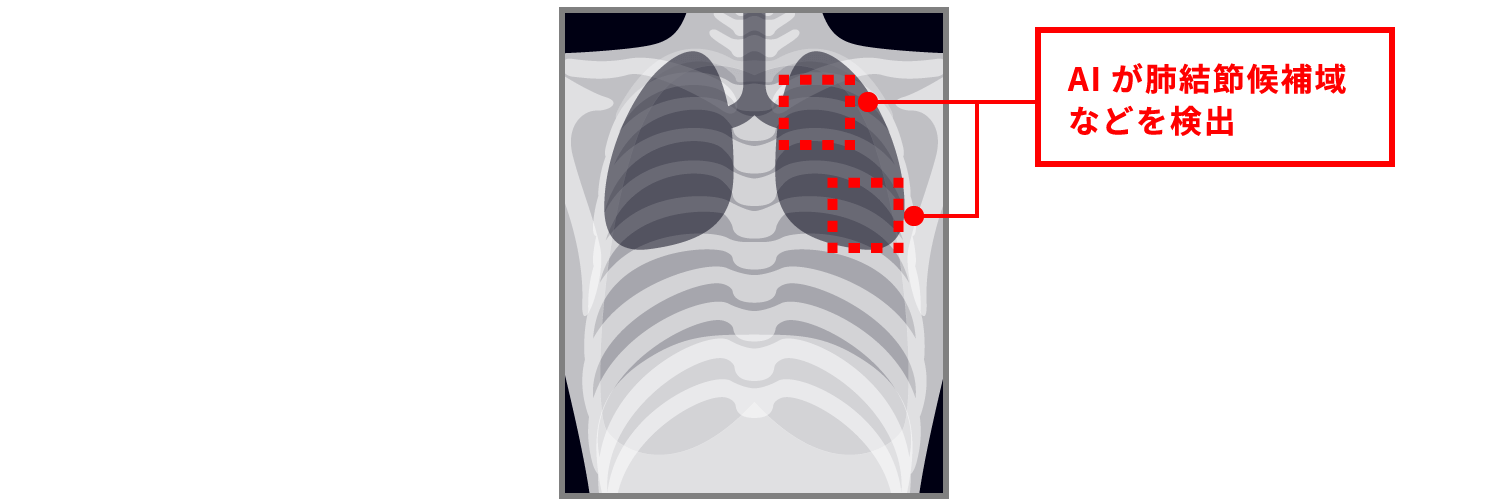

健診読影にAIを活用したい!

- 各メーカーのAIサービスと連携し、読影をサポート

- AIが肺結節影などの陰影を検出し、ビューア上に表示

- 陰影を検出した検査は、画像解析結果の確認を促す機能を搭載

撮影画像

AI解析画像

不安や悩む時間を軽減し、見逃しを防ぐ。

肺所見の指摘数の増加も見込めます!